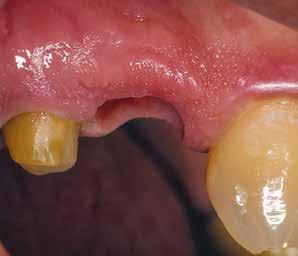

3. ábra: Bukkális lágyrészdefektus. — 4. ábra: A biológiai szélesség értékelése a vertikális lágyszövetvastagság alapján.

(2. ábra). A lágyszövetek értékelése Seibert szerinti I. osztályú csontdefektust állapított meg (3. ábra), ezért a beavatkozáskor palatinális „tekercslebenyt” preparáltunk (palatal roll flap), és implantációt végeztünk, hogy kompenzálni tudjuk a bukkális lágyszövet-behúzódást. Megmértük a vertikális lágyszövetvastagságot, és úgy terveztük, hogy a szubkresztális implantátum beültetése összhangban legyen a biológiai szélesség kialakulásával a transzgingivális gyógyulási periódus alatt (4. ábra)

Az eljárást helyi érzéstelenítés mellett végeztük (4%-os articaine-hidroklorid 1:100 000 adrenalinnal). Papillakímélő, U alakú palatális bemetszést végeztünk, teljes vastagságú nyálkahártyalebeny preparálás történt, a lebenyt bukkálisan feltekertük (5. ábra). A lebeny bukkálisan feltekert részén de-epitelizációt végeztük el, amellyel kompenzálni tudtuk a bukkális lágyszöveti defektust. Szakaszos előfúrást végeztünk, és a bredent copaSKY 4x10 implantátumot 30 Ncm behajtási nyomatékkal helyeztük be (6. ábra). Az implantátumot 1 mm-re szubkresztálisan helyeztük be, hogy később szélesebb emergenciaprofilt tudjunk kialakítani (7. ábra). Az egyedi ínyformázó úgy készült, hogy kompozitot vittünk fel a titánbázisra, és így formáztuk a lágyszöveteket a transzgingivális gyógyulási fázis során (8. ábra). Az egyéni ínyformázó tulipán formájú, hogy kialakítsa a kívánt emergenciaprofilt. A lágyszövetet feszülésmentesen zártuk #6/0 nem felszívódó, monofil fonallal (Optilene, B. Braun Deutschland; 9. a–b. ábra). Posztoperatív röntgenfelvétel készült, ami alapján az implantátum a szomszédos fogakkal párhuzamos elhelyezést mutatott (10. ábra). Posztoperatív utasításokat adtunk a páciensnek a műtéti terület körüli szájhigiénia fenntartása érdekében. A beavatkozást követő egy héttel a varratokat eltávolítottuk, és a kezelt terület kielégítő gyógyulást mutatott (11. ábra). A 4 hónap utáni késleltetett terhelést a páciens kívánsága szerint terveztük.

A késleltetett implantátumbeültetés egyik kihívása az extrakció utáni gerincatrófia kompenzálása. A horizontális és vertikális csontveszteség mértéke a foghúzást követő két éven belül akár a 60%-ot is elérheti, nagy része a foghúzást követő első hat hónapjában következik be [2]. A jelen esettanulmány egy kiszámítható lágyrészkezelési technikát mutat be, amelyet egyidejű implantátumbeültetéssel végeztünk. Módosított palatális „tekercslebeny” (rollflap) technikát alkalmaztunk a bukkális defektus kompenzálására és a megfelelőbb lágyszöveti kontúr elérése érdekében. A szabad szubepitheliális kötőszövet a grafttal ellentétben, a nyeleslebenynek köszönhetően nemcsak a gerincvolumennek jelent jobb vaszkularizációt, hanem megvastagítja a felszabadított implantátum körüli marginális gingivát is. A biotípus váltás vastagabb implantátum körüli nyálkahártyát hoz létre, és stabilabbá teheti a periimplantáris szöveteket [3]. Ez a megközelítés azért is előnyösebb, mivel nincs második donorterület, vagy nyílt seb, amely további fájdalmat és kellemetlenséget okozhatna a páciensnek a gyógyulási szakaszban. Mivel az implantátum beültetésével egyidejűleg történik, elkerülhető a további lágyszövet-augmentációs műtét. Ez javítja a páciens kényelmét és pozitív fogászati élményt biztosít. Szubkresztális implantátumbeültetést alkalmaztunk a transzgingivális gyógyulás során bekövetke-